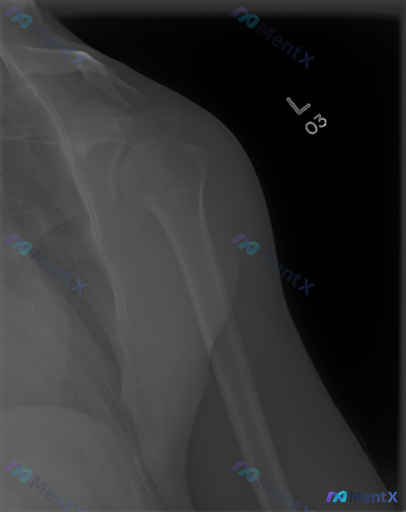

整理了一份左侧肩部正位X光片的资料,先看影像表现: - 肱骨近端、肩胛骨、锁骨远端骨皮质连续,未见明确骨折线/脱位 - 骨密度均匀,无明显骨质破坏或硬化 - 盂肱关节、肩锁关节间隙正常,无明显骨赘形成 - 肩周软组织无明显肿胀,冈上肌腱止点附近未见明确钙化灶 简单说:单看这份X光,骨性结构基本是“阴...